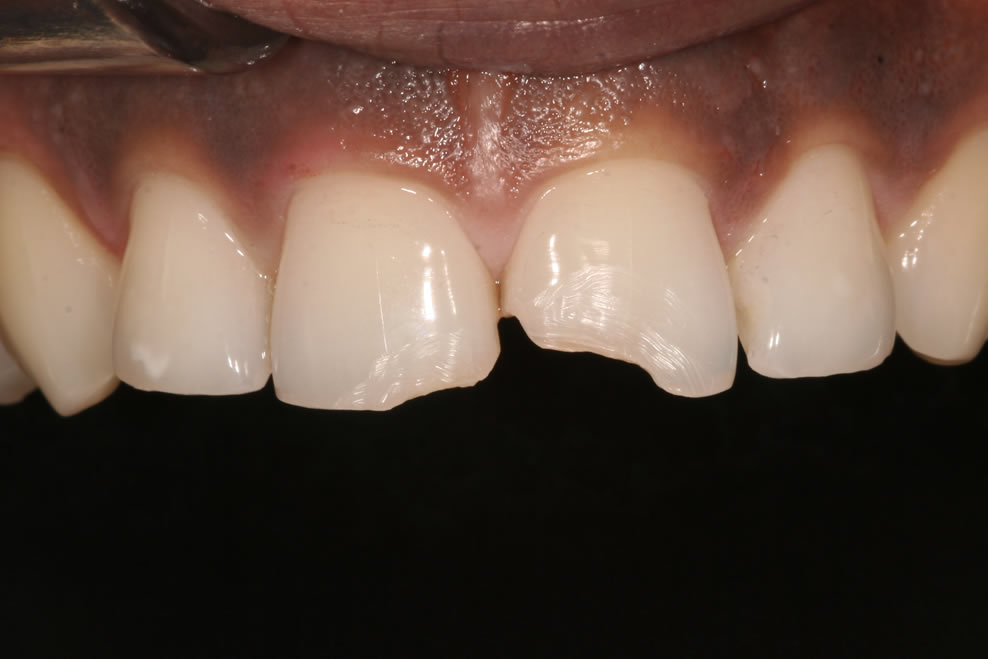

If you have a broken or decayed tooth, a composite filling can be used to restore the tooth to its original shape and colour.

Composite fillings can also be used for cosmetic purposes to restore chipped or uneven front teeth. Many patients also opt to have composite fillings used to replace old, unsightly silver fillings.